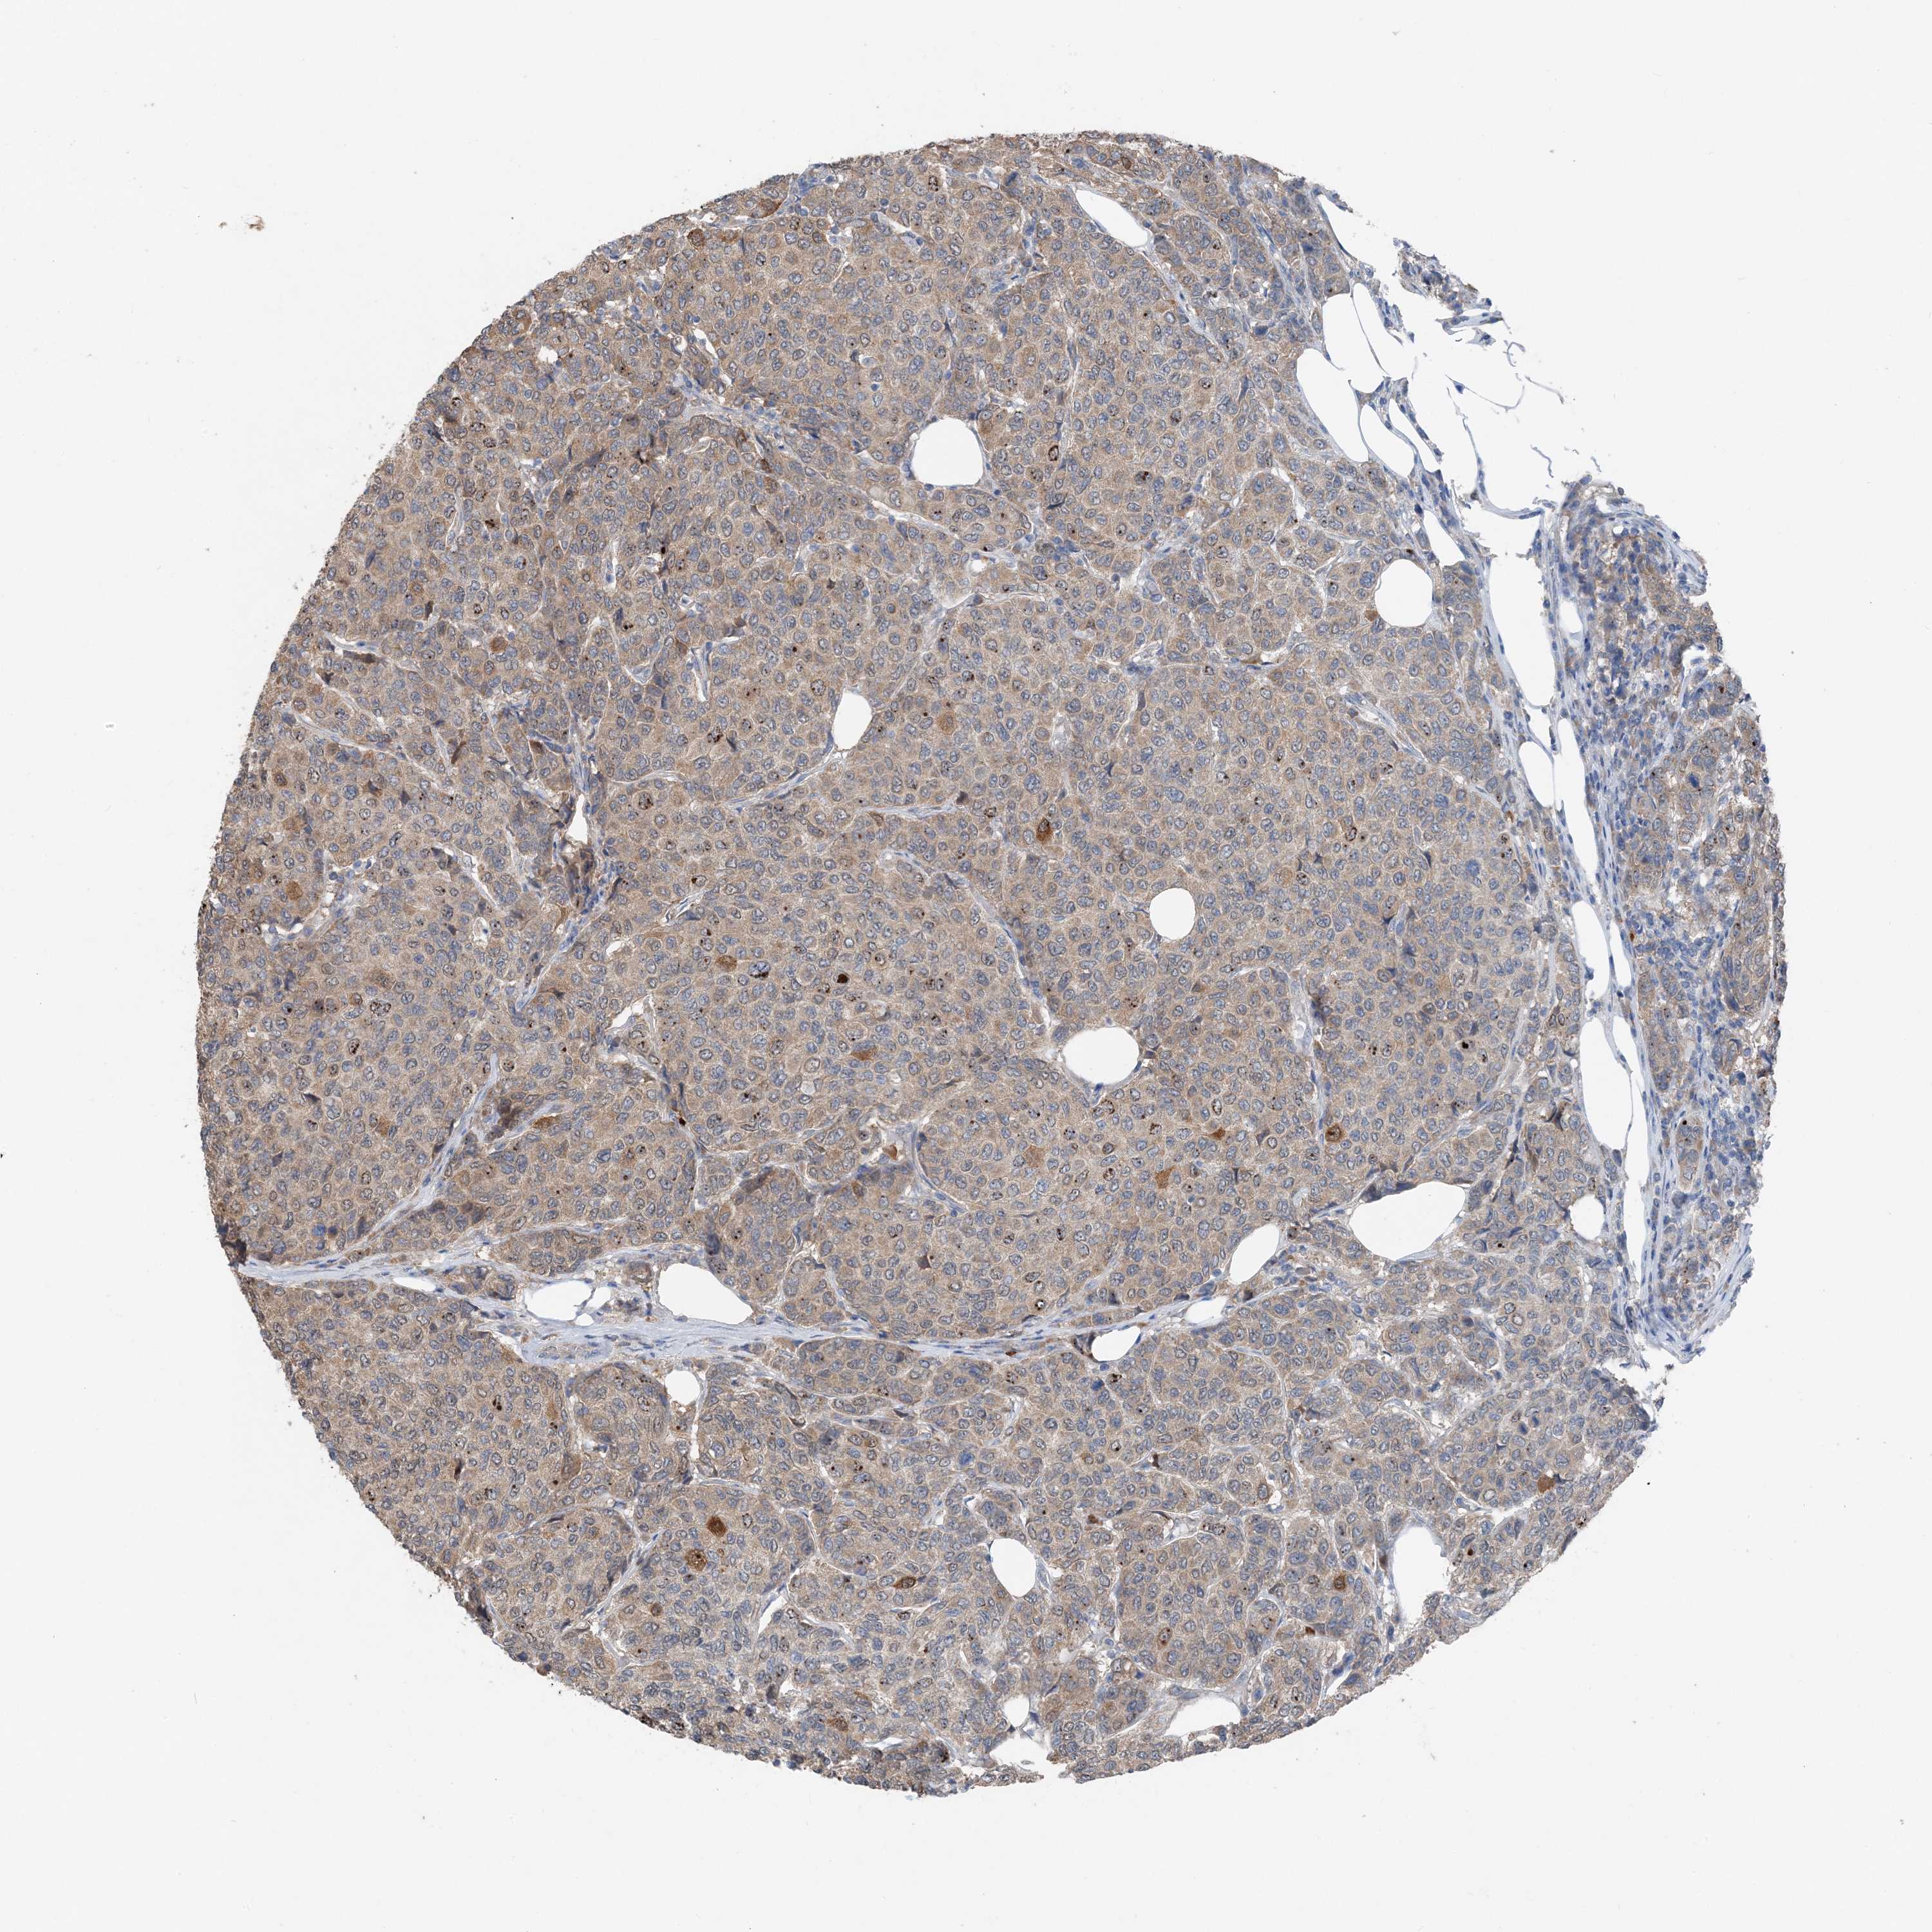

BRCA TCGA BRCA VALIDATION PROTEIN EXPRESSION

ANTIBODIES

AND

VALIDATION